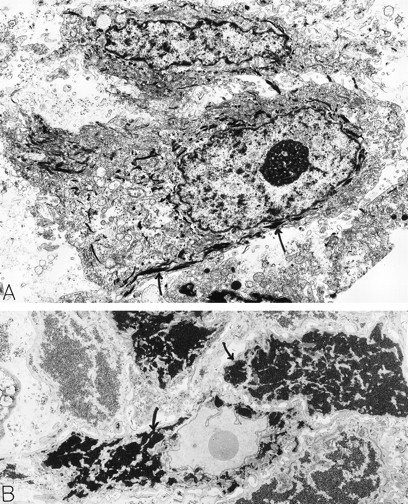

Squamous cell carcinoma. An 80-year-old man had a scalp lesion excised, which had been evident for three months. By light microscopy, this was a squamous cell carcinoma with an extensive clear cell component. Electron microscopy revealed typical squamous epithelial carcinoma cells attached by desmosomes and filled with bundles of electron-dense tonofilaments (arrows, A) in the cytoplasm. The clear cell component was comprised of glycogen-rich (B, arrows) squamous epithelial cells. The material for electron microscopy in (A) was processed by a standard method; in (B), the sample was postfixed in potassium ferrocyanide-reduced osmium to highlight glycogen stores which are electron dense (B, arrows). A: ×8,000; B: ×6,000. Original magnifications: (A), ×8,000; (B), ×6,000. (Courtesy of Ann M. Dvorak, MD, Beth Israel Deaconess Medical Center, 330 Brookline Ave, Boston, MA 02215.)